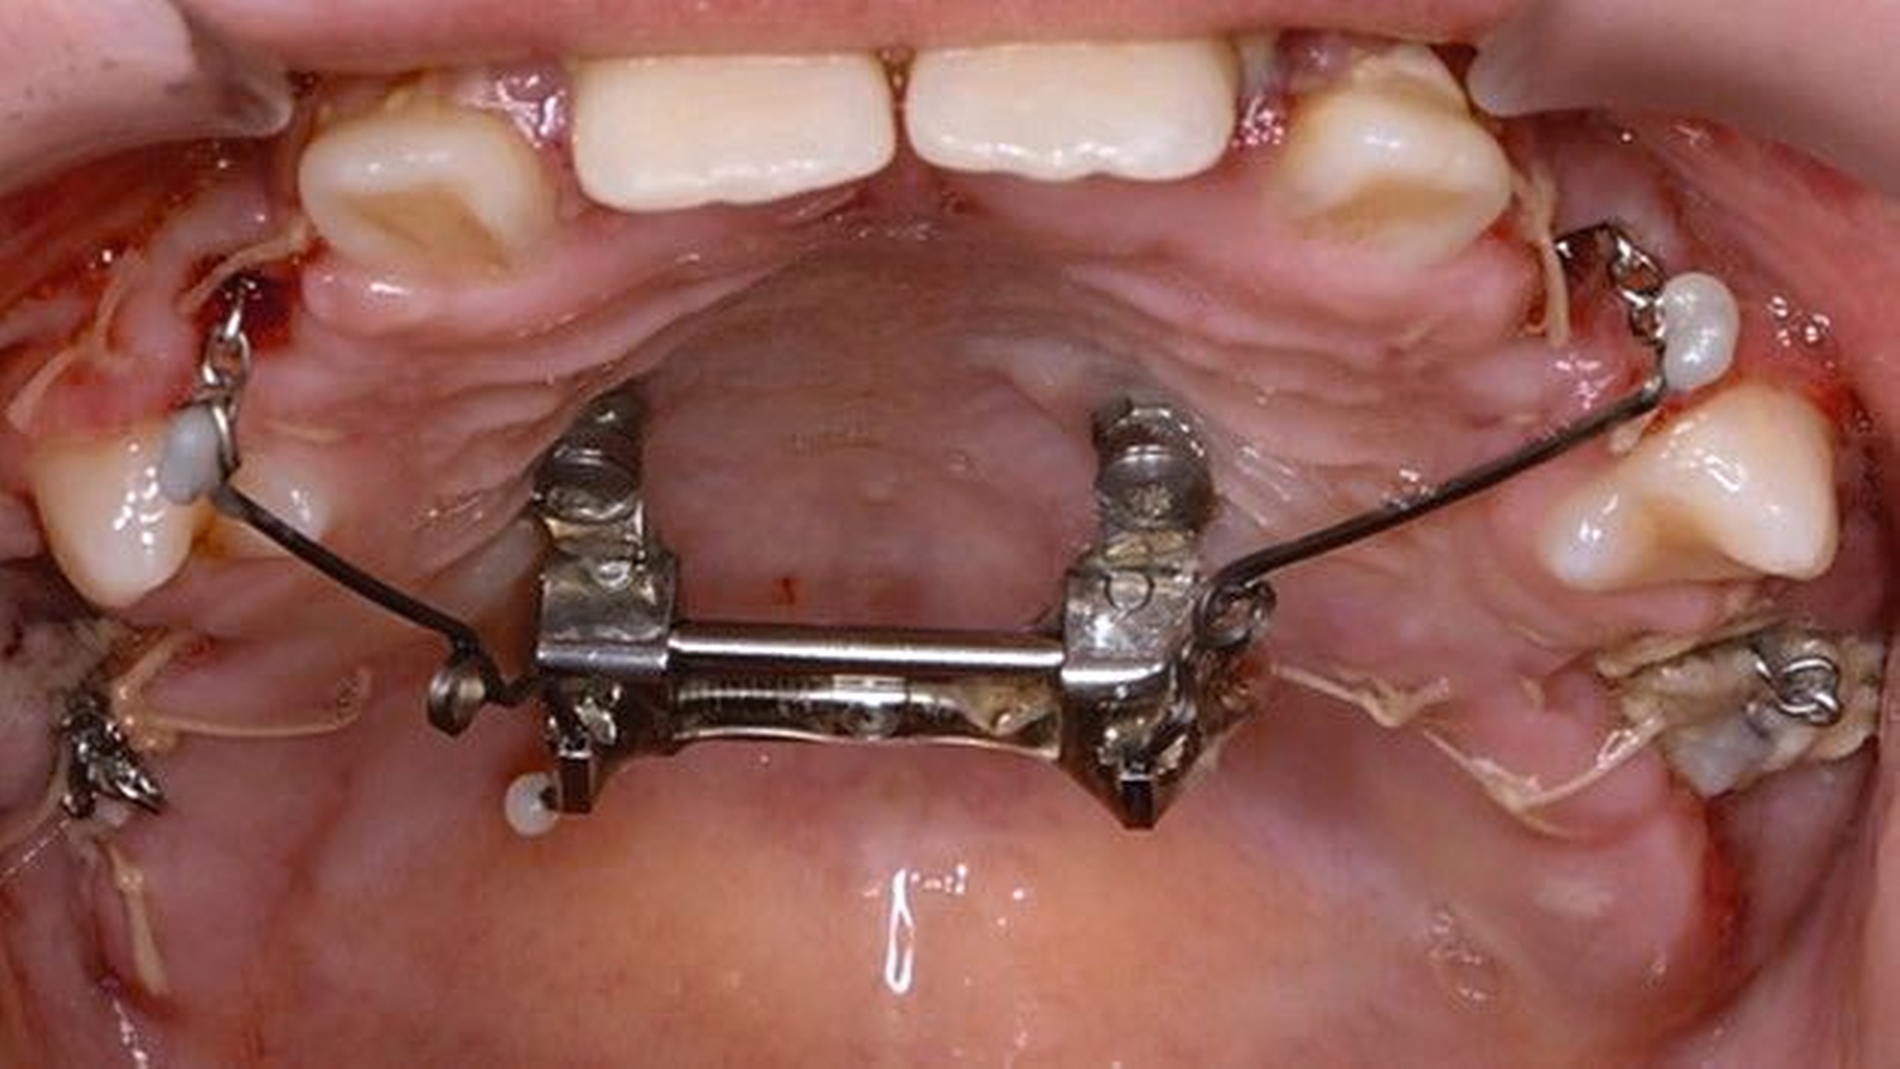

Die Zähne 36, 37, 46 und 47 wurden in Allgemeinanästhesie chirurgisch freigelegt. Zusätzlich wurden die beiden paramedianen Mini-Implantate (2 x 9 mm, Benefit System; PSM North America, Indio, CA) ohne Vorbohren mithilfe der zuvor hergestellten Schablone inseriert (Abbildung 3). Für die Platzierung der Mini-Implantate wurde ein Winkelschraubendreher verwendet. Direkt nach der Operation wurde die bmx DIRECT Hyrax-Schraube (10 mm, BENEfit®-System, Dentalline, Birkenfeld, Deutschland) an den Mini-Implantaten befestigt, um ein MARPE zu erzielen (Abbildung 4).

Die Eltern des Patienten wurden angewiesen, die Schraube einmal täglich zu aktivieren. Die gesamte Aktivierungszeit der Hyrax-Schraube betrug circa zehn Wochen. Während dieser Zeit vergrößerte sich die transversale Dimension des Oberkiefers um sieben Millimeter im posterioren Bereich (Milchmolaren) und um fünf Millimeter im anterioren Bereich (Milcheckzähne). Währenddessen trat ein mediales Diastema auf (Abbildungen 4b und 4c), das auf eine skelettale transversale Expansion des Oberkieferknochens hinwies. Nach der aktiven Expansionsphase der Hyrax-Apparatur wurde das Gerät für weitere Behandlungszwecke verwendet: Erstens als Retentionsgerät, um die bereits erzielte transversale Oberkieferbreite zu halten und zweitens als skelettal verankerte Apparatur zum Einstellen der retinierten und verlagerten Zähne mithilfe individuell angefertigter Kragarme. Hierfür wurde die Hyrax-Apparatur im zahntechnischen Labor modifiziert, indem Kreuzröhrchen für eine stationäre Befestigungen für die Drähte des Kragarms angebracht wurden.